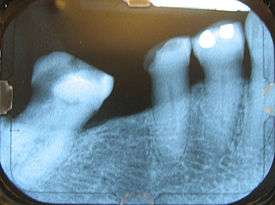

The alveolar process contains a region of compact bone adjacent to the periodontal ligament (PDL), which is called the lamina dura when viewed on radiographs. It is this part which is attached to the cementum of the roots by the periodontal ligament. It is uniformly radiopaque (or lighter). Integrity of the lamina dura is important when studying radiographs for pathological lesions.

The alveolar crest is the most cervical rim of the alveolar bone proper. In a healthy situation, the alveolar crest is slightly apical to the cementoenamel junction (CEJ) by approximately 1.5 to 2 mm.[3] The alveolar crests of neighboring teeth are also uniform in height along the jaw in healthy situation.[4]

The supporting alveolar bone consists of both cortical bone and trabecular bone. The cortical bone, or cortical plates, consists of plates of compact bone on the facial and lingual surfaces of the alveolar bone. These cortical plates are usually about 1.5 to 3 mm thick over posterior teeth, but the thickness is highly variable around anterior teeth.[3] The trabecular bone consists of cancellous bone that is located between the alveolar bone proper and the plates of cortical bone. The alveolar bone between two neighboring teeth is the interdental septum (or interdental bone).[4]